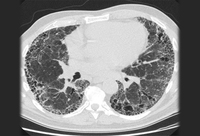

Chest CT scan image of idiopathic pulmonary fibrosis

From the collection of Jeffrey C. Munson, MD, MS; used with permission